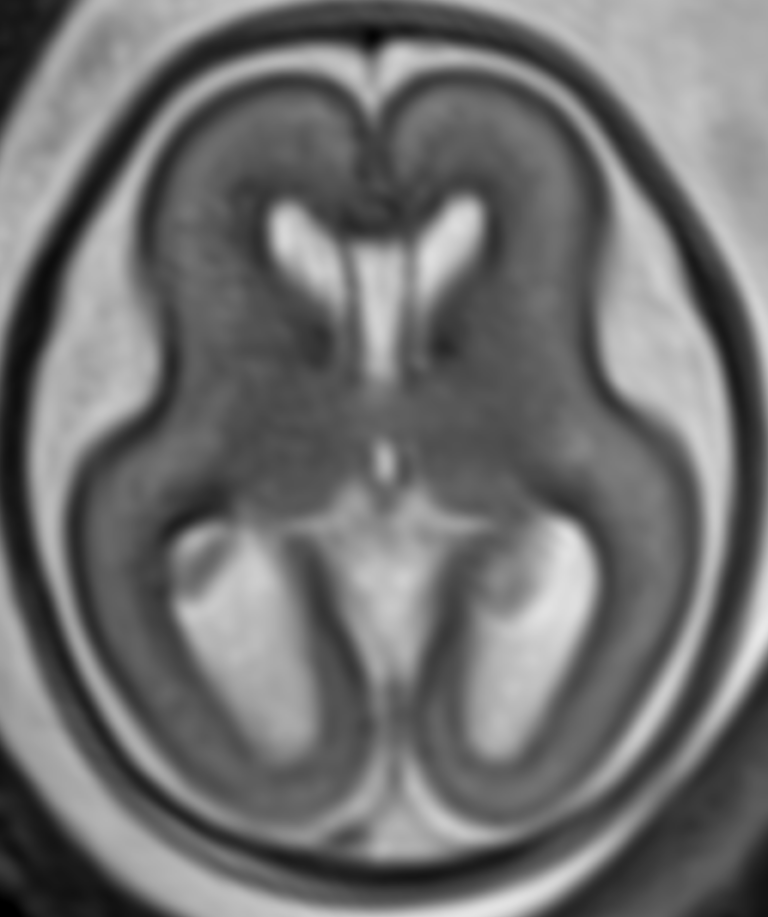

Anne karnındaki bebeğin beyin gelişimi çok karmaşık ve hassas bir süreçtir. Rutin ultrasonda fark edilen bazı bulguların daha ayrıntılı değerlendirilmesi gerektiğinde, fetal MRG (manyetik rezonans görüntüleme) devreye girer.

Fetal MRG ile:

Beyin boşluklarındaki sıvı artışı (ventrikülomegali)

Beyincik veya beyin sapındaki yapısal bozukluklar

Beyin kıvrımlarındaki gelişimsel farklılıklar

gibi durumlar net şekilde görüntülenebilir. Bu sayede bebeğinizin doğum sonrası ihtiyaç duyabileceği tıbbi destekler planlanabilir.